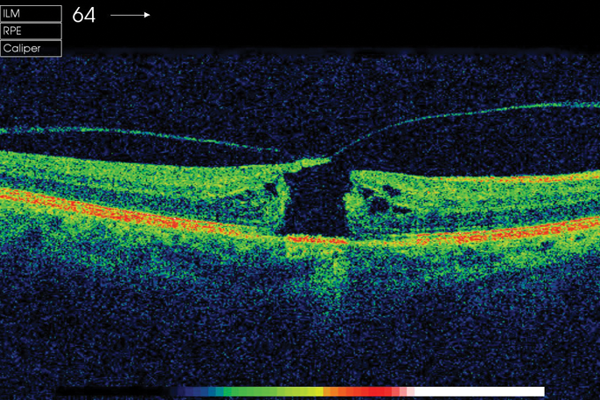

Macular holes: A brief review

Tina Parmar

·

1st June 2017

Education